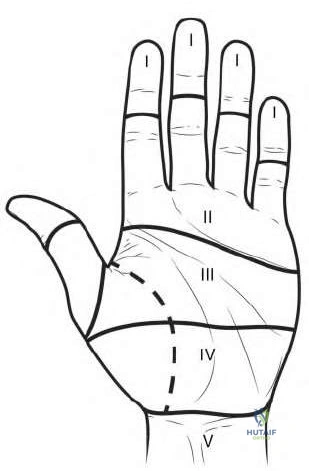

A 24-year-old male falls on an outstretched hand and sustains a fracture of the scaphoid waist. He is evaluated for surgical fixation due to displacement.

A 42-year-old diabetic male presents with severe swelling, erythema, and pain in his right middle finger after a minor puncture wound. You suspect pyogenic flexor tenosynovitis.

A 25-year-old patient suffers a severe crush injury to the hand. Clinical evaluation raises suspicion for compartment syndrome of the hand. How many distinct fascial compartments are recognized in the hand that may require release during fasciotomy?

A patient develops a purulent infection spreading from the flexor tendon sheath of the small finger into the palm, which subsequently travels up into the flexor tendon sheath of the thumb. This specific pattern, known as a 'horseshoe abscess,' occurs through an anatomical connection between which two spaces?